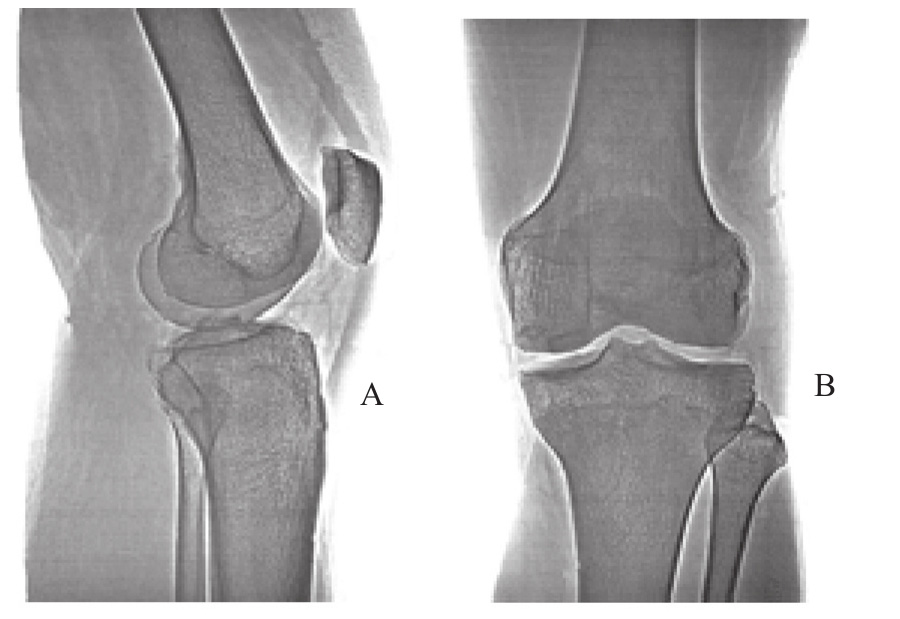

图2.11 膝关节X线片

A.侧视图;B.后视图

在解剖学上,当膝关节面对直接来自外侧的横向外力与旋转力时,胫骨平坦的关节表面并无法给予大腿骨的半圆部分(骨节)足够的支撑。由于此机制是如此的精细且复杂,尽管半月板增加了一些支撑,整个关节机制仍旧非常脆弱(图2.11)。